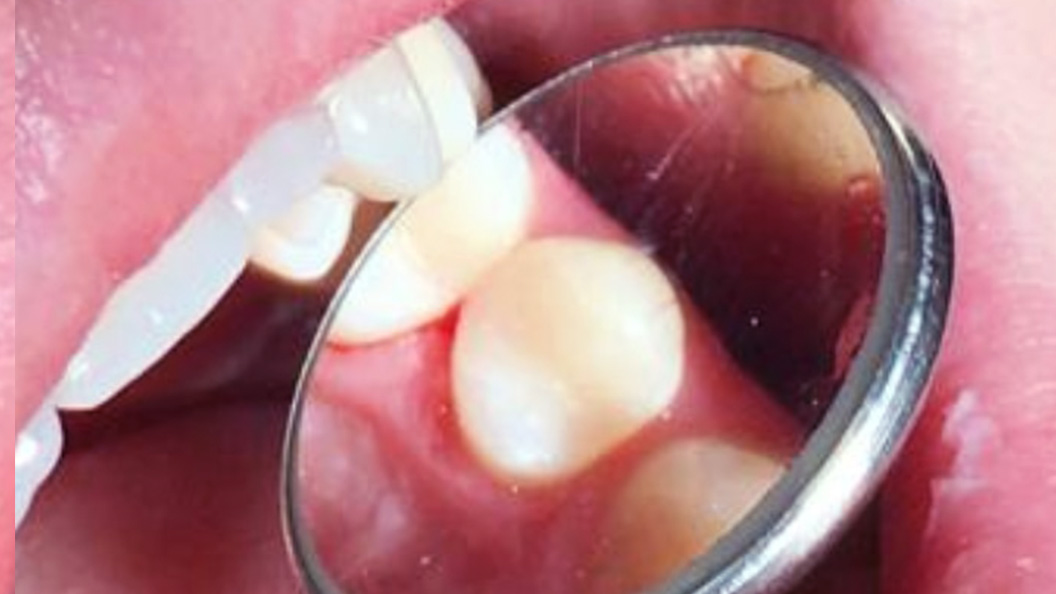

До и после лечения

В процессе лечения врач провёл следующие манипуляции:

- анестезия;

- изоляция зуба перед лечением;

- очищение и формирование кариозной полости;

- установка светового композита и его фиксация;

- шлифовка и полировка готового зуба.